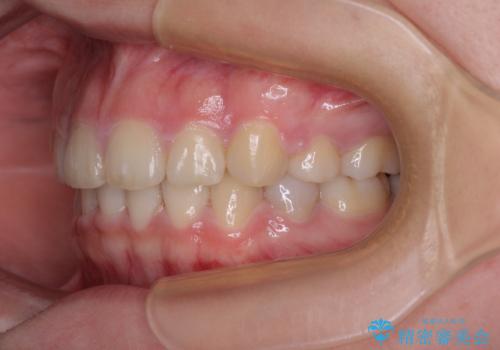

舌の突出癖があり、咬合力も強かったため、治療期間は長くなることが懸念されましたが、舌のトレーニングをしっかりと行っていただいたこともあり、2年弱で治療を終えることができました。

上下ともに歯列が前方に突出していたため、上下左右の第一小臼歯4本を抜去する方針(既に上顎は抜歯されています)で、ワイヤー装置による矯正治療を行うこととしました。